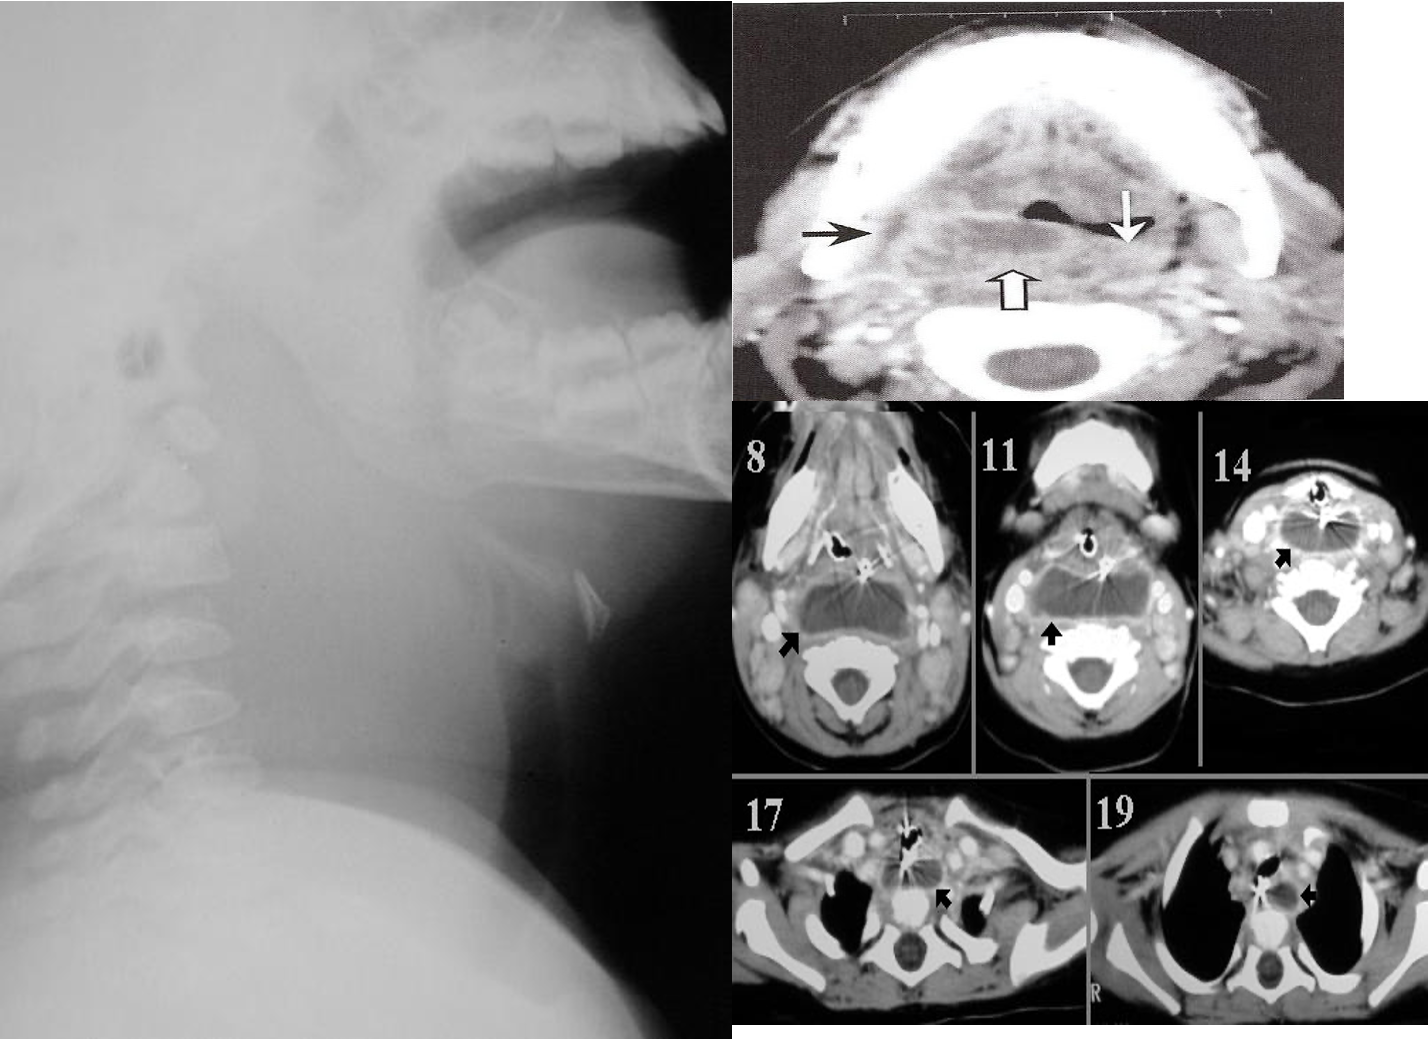

Complication

- mediastnitis

- respiratry distress

- rupture abscess

- Transoral incision and drainge